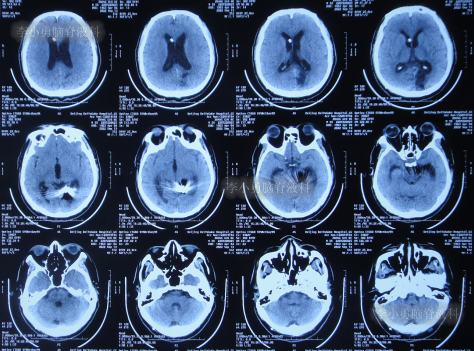

患者于2022年3月16日早晨起床后,无诱因突发头痛,恶心及呕吐,嗜睡,急就诊于当地黑龙江省海伦市某医院,查头颅CT扫描脑出血(片子丢失),因技术有限,120急救车转至上级的黑龙江省哈尔滨某三甲医院,再次复查头颅CT示出血量无明显增多(片子丢失),当天给予脑室外引流术,脑室外引流术后次日查头颅CT示脑出血脑室引流术后(图-1),医生考虑为动脉瘤出血。

图-1:2022年3月17日头颅CT

2022年3月23日(脑动脉瘤栓塞术后5天),查头颅CT示积血减少(图-3);术后身体恢复良好,能自行下地活动。

图-3:2022年3月23日头颅CT

2022年4月27日(入院治疗3天),脑脊液培养出细菌,给予抗感染治疗,查头颅CT示脑室扩张加重(图-5)。

图-5:2022年4月27日头颅CT

抗感染治疗28天即2022年5月25日,查头颅CT示仍脑积水(图-6),脑脊液仍有细菌。

图-6:2022年5月25日头颅CT

抗感染治疗41天即2022年6月7日,脑脊液化验细菌消失,但查头颅CT示仍脑积水(图-7)。

图-7:2022年6月7日头颅CT

2022年6月13日(脑室腹腔分流术后5天),术后患者仍走路不稳,有时胡言乱语,言语不清,小便失禁,查头颅CT(图-8)示脑室仍有扩张。

图-8:2022年6月13日头颅CT

2022年6月17日(分流术后9天即第2次该院治疗53天),查头颅CT虽仍有脑积水(图-9),但仍让患者出院,出院时:仍走路不稳,有时胡言乱语,言语不清,小便失禁;转至当地的某医院进行治疗。

图-9:2022年6月17日头颅CT

在当地的某医院进行康复治疗1个月的时间,患者症状无改善,期间3次查头颅CT(图-10、图-11、图-12)均示仍脑积水。

图-10:2022年6月20日头颅CT

图-11:2022年7月1日头颅CT

图-12:2022年7月12日头颅CT

入院时查头颅CT示脑室分流术后仍脑积水(图-14)。

图-14:2022年7月22日头颅CT

2022年9月13日(住院治疗53天),常规查头颅CT示脑室引流术状态(图-22)。

图-22:2022年9月13日头颅CT

2022年10月11日(住院治疗80天),进行了脑室腹腔分流术。脑室腹腔分流术次日查头颅CT和身体均无异常(图-23)。

图-23:2022年10月12日头颅CT

2022年12月9日(李小勇脑脊液科治疗4月余)出院,出院时:身体一切正常(图-24),头颅CT未见异常(图-25)。

图-25:出院时头颅CT